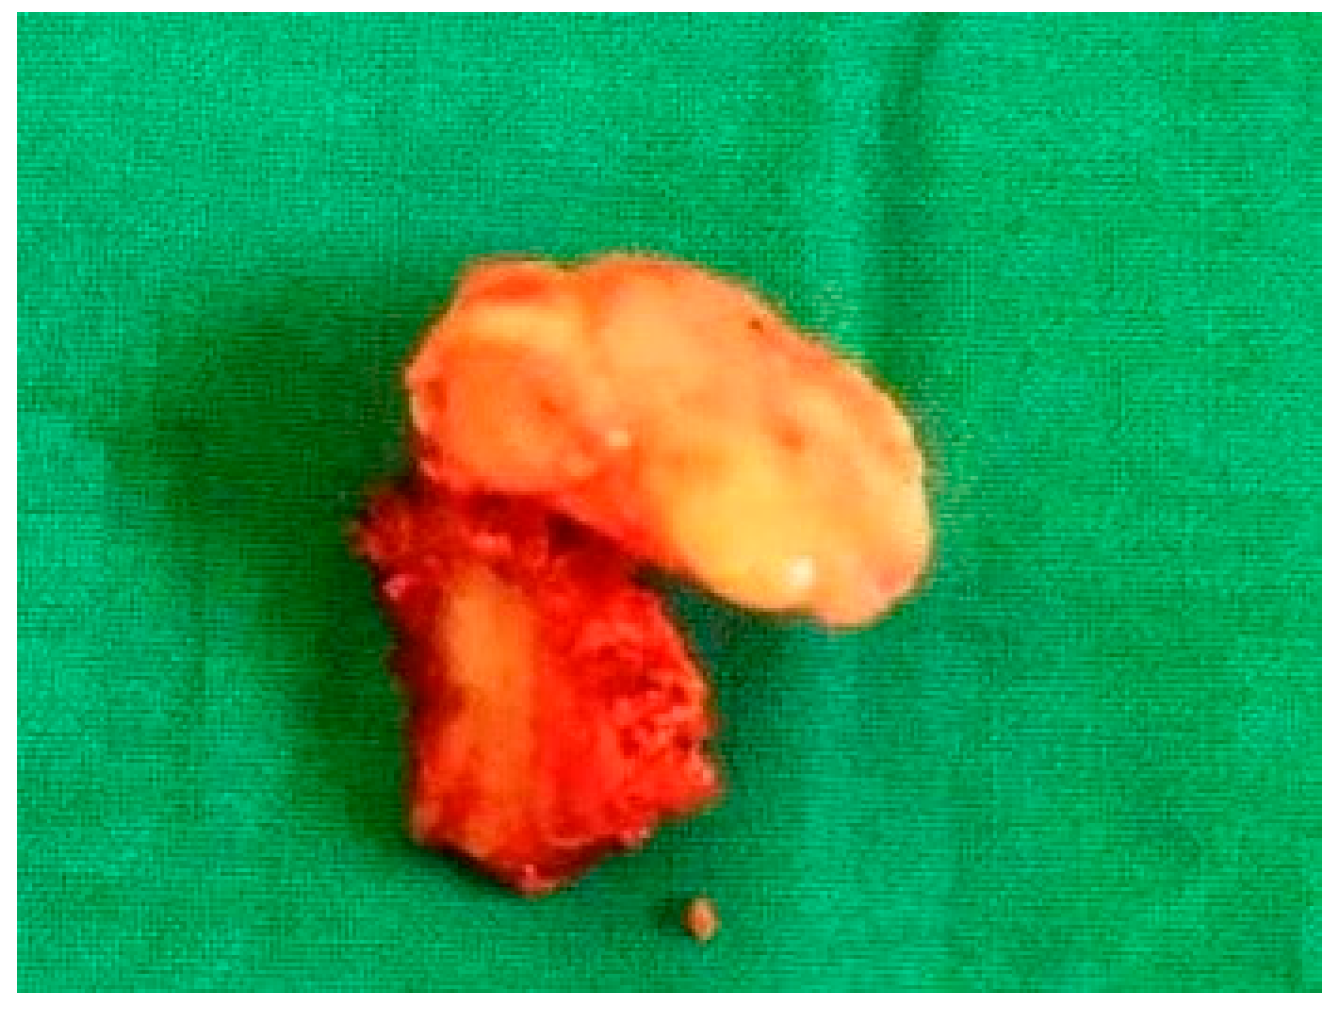

- Case 1

- Case 4